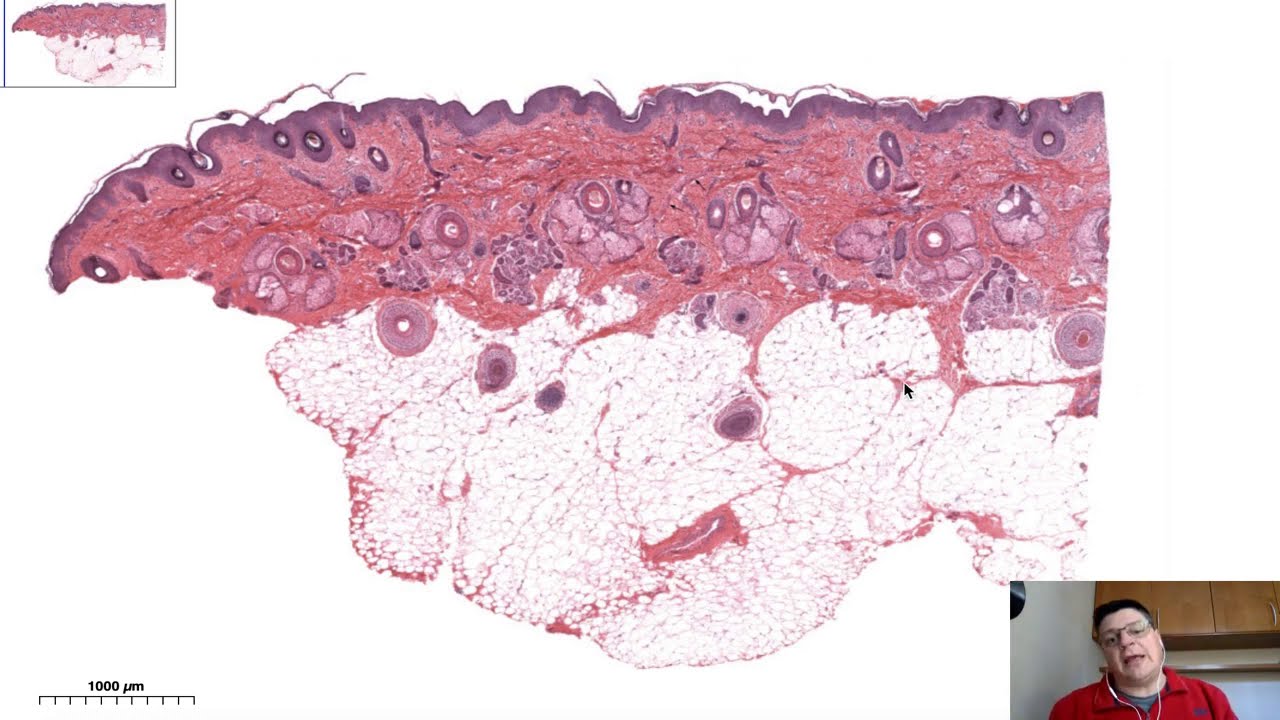

o Olá pessoal então nós vamos para mais uma vídeo aula onde hoje nós vamos tratar de fígado e pâncreas que são glândulas acessórias ao sistema digestório nós vamos ver que elas não atuam somente no sistema digestório É então A ideia é nós trabalharmos com a estrutura histológica dessas duas plantas bom nesse primeiro corte Aqui nós temos um quarto histológico de fígado corado com hasan E por que que ele foi curado com as a justamente para facilitar a visualização dos lóbulos hepáticos O que é a principal característica histológica do fígado tá então quando a gente olha

a essa imagem é a gente vê que os lóbulos hepáticos algo fígado é um órgão parenquimatoso com cápsulas septos Só que os lóbulos hepáticos é eles tem um formato diferente dos e de todas as outras glândulas que são arredondados os lóbulos hepáticos eles são poligonais como a gente vê nesse exemplo aqui e nós vemos também que no centro do lóbulo hepático existe o que te conhece por veia centro lobular e em cada canto desse lóbulo hepático como eu tô mostrando aqui para vocês neste canto nesse canto nesse outro e assim sucessivamente tem o que se

conhece por espaço porta esse espaço porta contém 13 estruturas que formam o psi conhece por Tríade Portal bom o fígado ele é um órgão que ele tem funções bastante variadas desde função de detoxificação a função de armazenar glicogênio função de armazenar lipídio e armazenar diferentes tipos de vitamina e mais relacionada ao sistema digestório o fígado tem a função de produzir bile também é importante nós nós é relembrarmos que 75 por cento do sangue que chega no fígado ele vem a partir do sistema porta a partir da veia porta que recolhe o sangue do intestino do

aqui aqui o foco é nós trabalhar nos quais histologia Então para que a gente na mitologia eu já comentei da veia centrolobular do espaço porta e da cria de Portal Então nós vamos olhar aqui dentro desse lóbulo hepático nós vamos ver a veia centro lobular essa veia centro lobular como vocês vem depois nós vamos ver um pouco mais de detalhe é onde desembocam os sinusóides hepáticos então quando a gente aumenta um pouco aqui coloca a imagem um aumento um pouco maior a gente vê os hepatócitos que são essas células aqui que compõem a maioria do

parênquima hepático vários hepatócitos são binucleadas como a gente ver um exemplo aqui e entre os hepatócitos estão os sinusóides hepáticos tá então o que que a gente precisa compreender que a circulação sanguínea no fígado ela se dá a partir do espaço porta e chegam é dentro como componentes dessa trilha de Portal artéria hepática e a veia porta e o sangue se desloca do desse local aqui dois passo porta e em direção a veia centro lobular por isso que é dito que a circulação sanguínea no fígado é centrípeta ou seja ela é da borda do lóbulo

para o centro do lóbulo hepático E durante esse processo é que acontece em todas as modificações que o sangue é sofre ao passar pelo fígado dentro das funcionalidades desse hora bom é quando nós olhamos o os espaços portas nós temos os exemplos de trilha de Portal esse aqui não tá muito claro mas vocês veem vasos venosos bem calibrosos aqui Aqui nós temos um o e de trilha de Portal um pouco mais definido onde nós temos vasos arteriais que trazem sangue venoso vindo do coração vasos venosos que trazem sangue venoso vindo do intestino e nós temos

os ductos biliares que carreiam abinee de dentro do lóbulo para fora que daqui a pouco a gente explica um pouco mais Então esses ductos biliares que aqui nós que são formados por epitélio cúbico simples eles levam o a Billy a partir do lóbulo hepático para para o ducto e vesícula biliar dependendo do momento bom é tendo-o visto essa estrutura geral Aqui nós temos o mesmo corte de fígado só que ao invés de tá curado com azeite acordar o h é com hematoxilina E eosina então nós conseguimos ver também O lóbulo hepático ele não fica tão